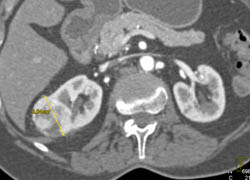

Vascular Renal Cell Carcinoma